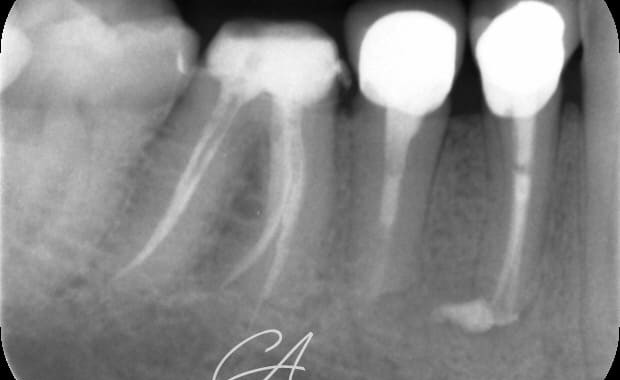

Buongiorno a tutti, oggi mi piacerebbe condividere con voi un caso multidisciplinare. Il paziente si presenta per ricorrenti ascessi in sede 45 e 44. Entrambi gli elementi vengono sagomati con strumenti espansivi. L'elemento 44 viene otturato con tecnica single cone e bioceramico mentre l'elemento 45, a causa del diametro importante (> 80) e per la forma ovale del sistema endodontico, viene sottoposto ad apical plug in MTA. Gli elementi vengono poi sottoposti a fase ricostruttiva (in seguito a disassembling delle corone) e limati con tecnica BOPT e il provvisorio viene mantenuto diversi mesi per condizionare i tessuti. Tutto bene, fino a quando non mi sono fatto realizzare le corone definitive. Ho notato subito che avrei ottenuto una vistosa disomogeneità dei livelli gengivali; ho pertanto deciso di proporre al paziente (a mie spese), un innesto gengivale libero per l'ispessimento dei tessuti gengivali. Ho quindi modificato la lunghezza e il profilo di emergenza della corona 44 e cementate entrambre le corone con cemento provvisorio in attesa della maturazione dei tessuti.

Il controllo dei tessuti gengivali è ancora precoce ma la guarigione radiografica periapicale è a 1 anno (ultima radiografia visibile).